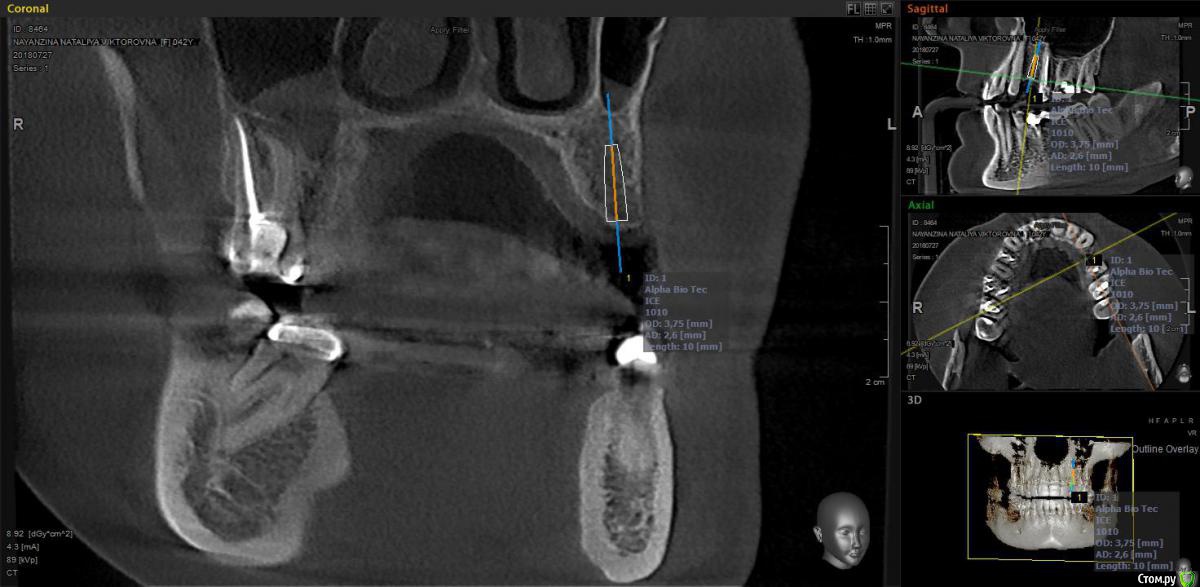

moises Опубликовано 8 августа, 2018 Автор Поделиться Опубликовано 8 августа, 2018 Я бы просто заглубил и поставил более небно, там дальше миллиметров 6 есть, 4х10 винт должен влезтьВот так примерно? А вестибулярно косточку сглаживать или как есть этот козырек оставить? Ссылка на комментарий

kramer Опубликовано 8 августа, 2018 Поделиться Опубликовано 8 августа, 2018 Вот так примерно? А вестибулярно косточку сглаживать или как есть этот козырек оставить? Ничего не сглаживать, винт глубить сильнее Ссылка на комментарий

Aquarius Опубликовано 8 августа, 2018 Поделиться Опубликовано 8 августа, 2018 Кость - почти подарок. Наклон только выровняйте. Чтобы имплант шел четко между зубами. После пилотного сверла, его оставьте в ложе и с ним же сделать снимок ( если в наборе нет пинов параллельности). Ссылка на комментарий

Дмитрий Л. Опубликовано 16 августа, 2018 Поделиться Опубликовано 16 августа, 2018 Да, протезируюНу тогда странный выбор позиции в первом посте) Кость - почти подарок. Наклон только выровняйте. Чтобы имплант шел четко между зубами. После пилотного сверла, его оставьте в ложе и с ним же сделать снимок ( если в наборе нет пинов параллельности). +1 и ещё бы добавил: с пилотным сверлом или пином в лунке попросите прикрыть рот и проконтролируйте направление оси имплантата относительно нижнего зуба. Ссылка на комментарий